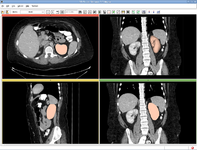

| + | Image:Registration_BRAINSfit.png|NEW: [[Modules:BRAINSFit |BRAINSFit Registration]] (Hans Johnson) | ||

| + | Image:Registration_BRAINSdemonwarp.png|NEW: [[Modules:BRAINSDemonWarp|BRAINSDemonWarp]] (Hans Johnson) | ||

NEW: BRAINSFit Registration (Hans Johnson)

NEW: BRAINSDemonWarp (Hans Johnson)